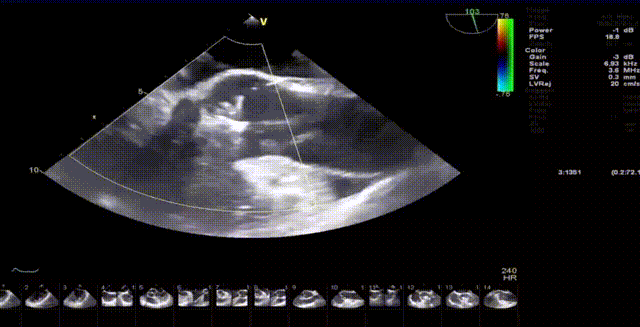

术前超声

手术过程顺利,器械操作用时仅10分钟。术中通过造影确认右冠窦居中,定位件准确入窦,瓣膜释放顺利。经超声评估,无瓣周漏,手术过程衔接流畅,未出现其他特殊情况。

术后患者恢复良好,心功能显著改善。影像复查显示瓣膜功能正常,无反流及瓣周漏,未见心律失常、出血等并发症。平均主动脉跨瓣压差5mmHg,整体状态稳定,心功能与生活质量均有明显提升。